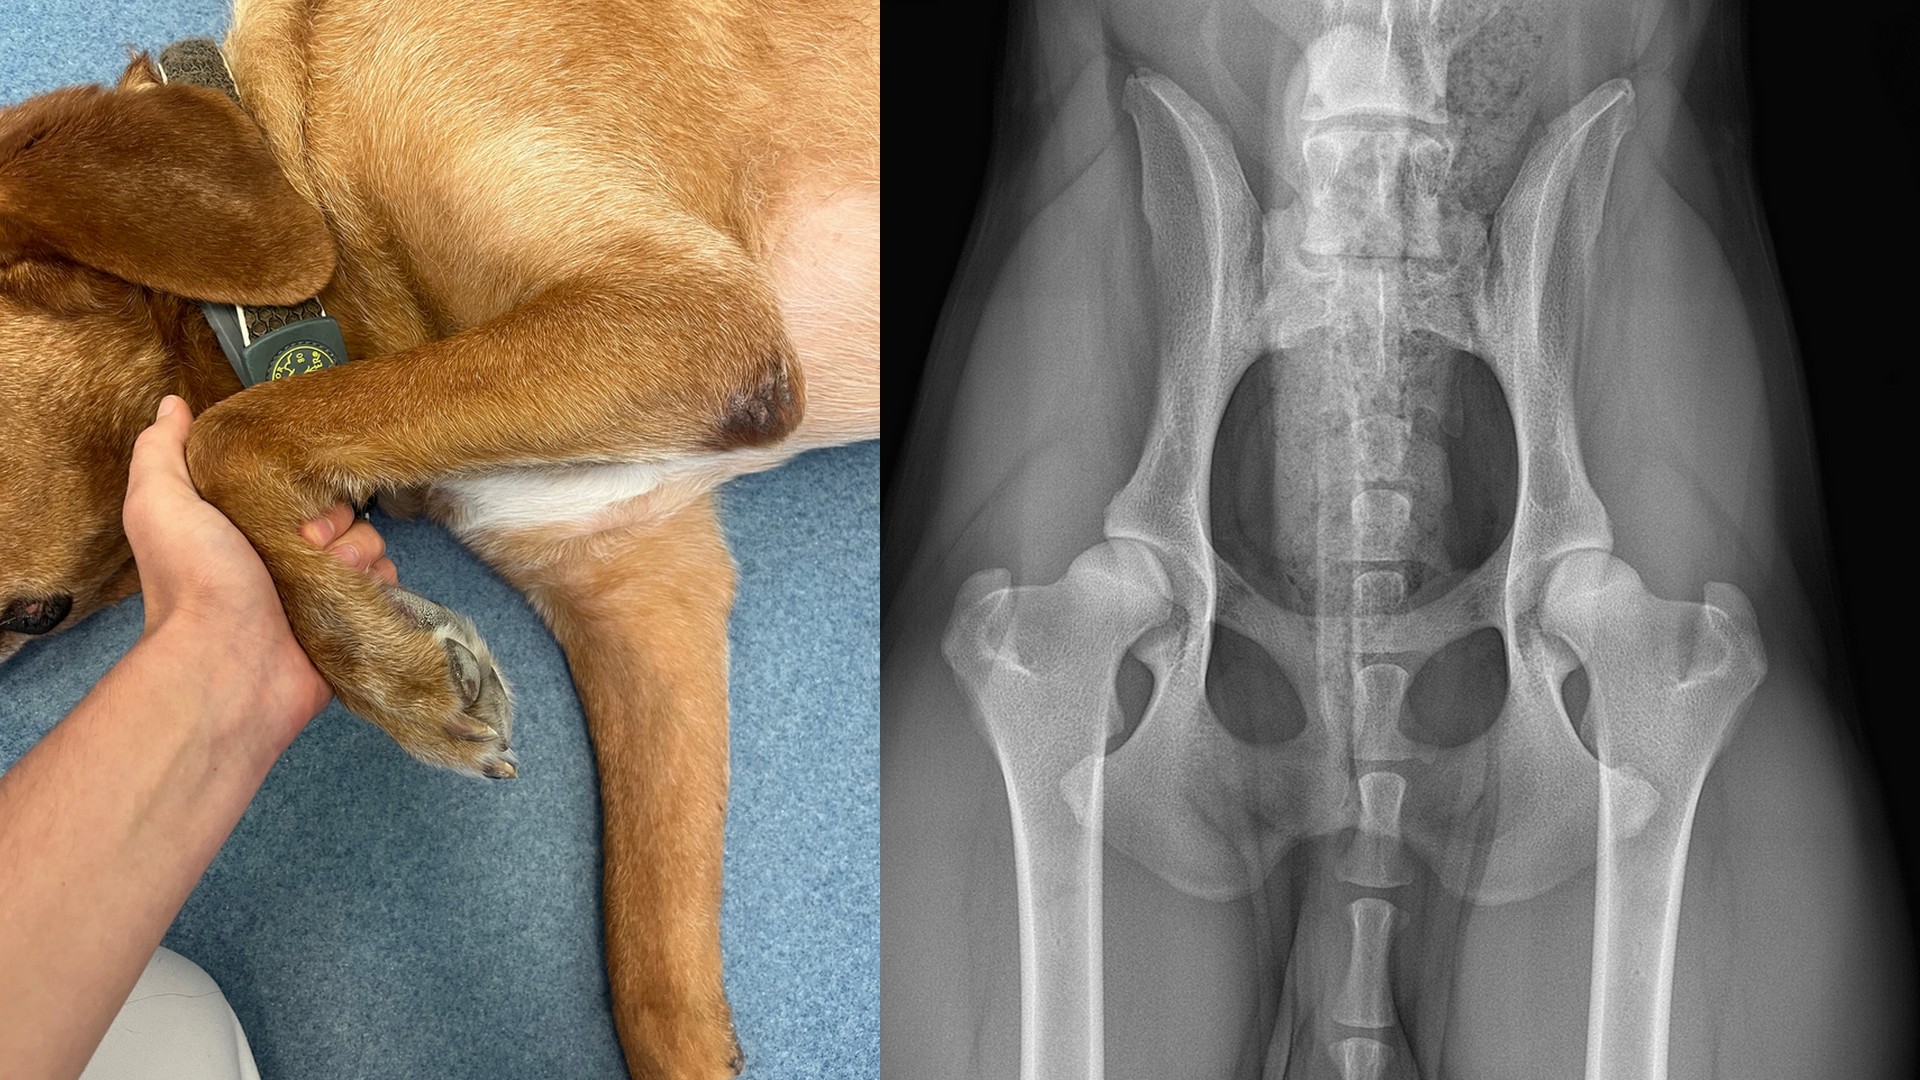

Ein zentraler Schwerpunkt des Kurses liegt auf den typischen Gelenkerkrankungen des Hundes. Dabei wird für jedes wichtige Gelenk eine häufige, charakteristische Erkrankung kurz und verständlich besprochen – von der Vordergliedmaße bis zur Hintergliedmaße. So erhältst du einen strukturierten Überblick über Lahmheitsursachen von vorne nach hinten und lernst, typische Bewegungsauffälligkeiten besser einzuordnen.

Du erfährst unter anderem, welche Probleme im Schulter-, Ellbogen-, Karpal-, Hüft-, Knie- und Tarsalgelenk auftreten können und wie sich diese Erkrankungen im Bewegungsbild zeigen – etwa Osteochondrosen, Gelenkdysplasien, Bandverletzungen oder arthrotische Veränderungen.

Lektion 6: Hüftgelenk, Hüftgelenksdysplasie